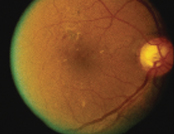

| 黃斑水腫 | |

![]() 治療後 |